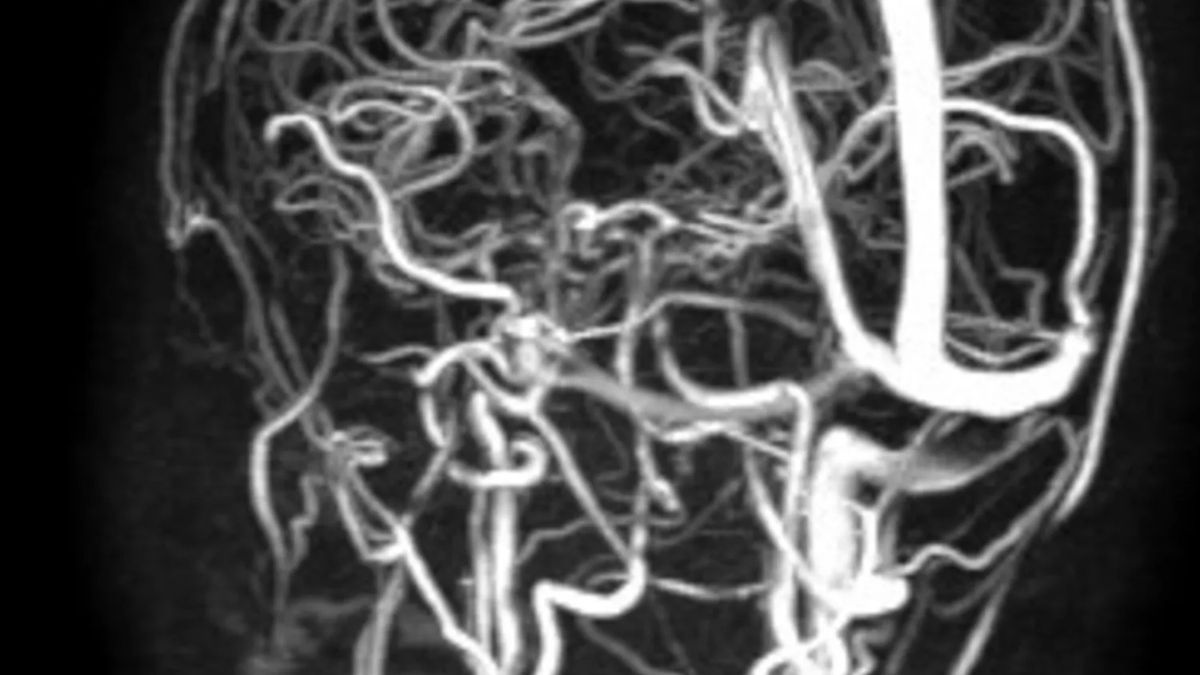

L’équipe di Otorinolaringoiatria, diretta da Nicola Quaranta, ha eseguito un drenaggio trans-timpanico per eliminare l’infezione responsabile della trombosi. Parallelamente, la Neurochirurgia, guidata da Francesco Signorelli, ha effettuato una derivazione spinale esterna. Questo secondo intervento ha consentito di ridurre indirettamente la pressione intracranica e la compressione esercitata sui nervi ottici, fattori determinanti per il recupero della funzione visiva. Dopo tre settimane la derivazione è stata rimossa e la bambina dimessa. Al controllo a sei mesi, la trombosi risultava quasi del tutto risolta e la vista completamente recuperata. 🔗 Leggi su Thesocialpost.it